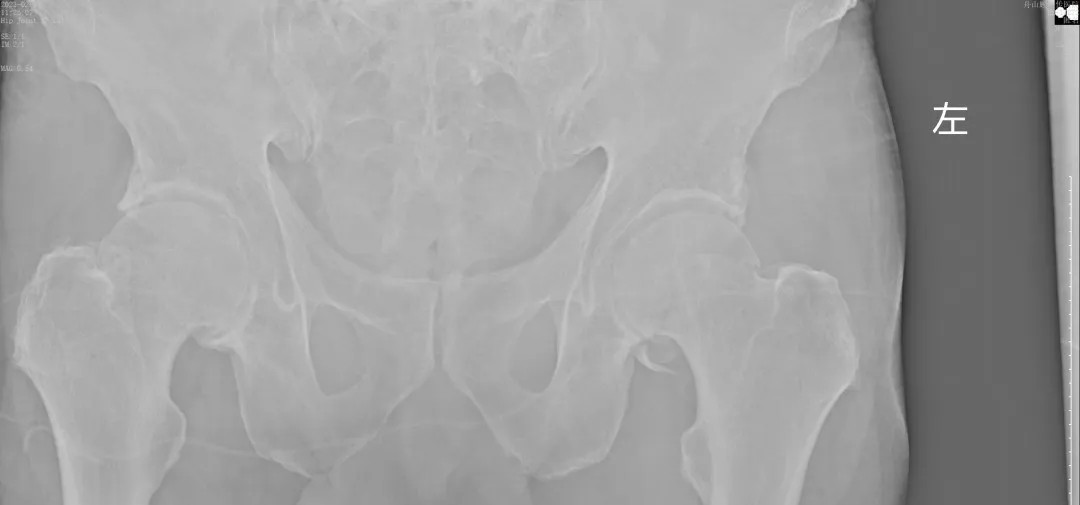

经过王副主任认真仔细的检查,并结合X线摄片后,他告诉患者及其家属:“周大爷是外伤导致的急性髋关节脱位、髋臼骨折!”一听脱位骨折了,患者及家属焦虑万分,担心手术给身体和经济带来的巨大压力。王副主任耐心告知周大爷一家人:“周大爷这种病情可以保守治疗,用我们顾氏的正骨手法可以复位的,不需要开刀,价格也实惠”。家属听到不用做手术,瞬间放心不少,表示非常愿意配合治疗。

(术后复片  关节对位良好)